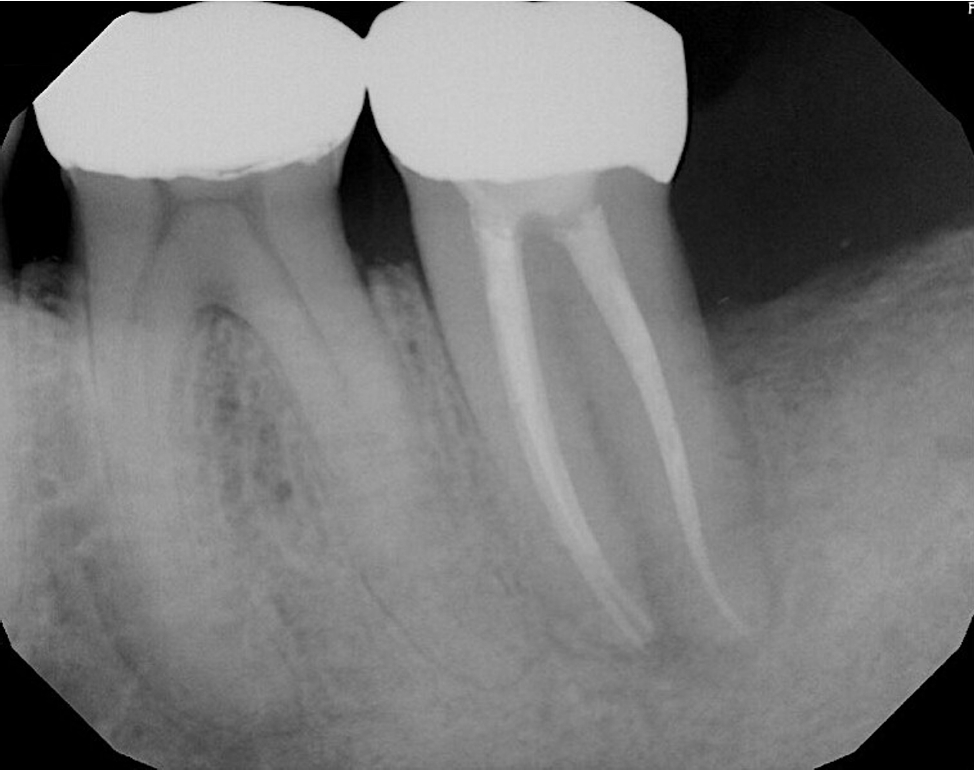

Radiographically, a “J-shaped” lesion was observed along the distal root of #18 (Figure 1), suggestive of a primary endodontic lesion with secondary periodontal involvement. A radiopaque fragment, consistent with a cemental tear, was identified along the distal root surface (Figure 1).

Figure 1.

“J-shaped” lesion observed along the distal root of #18 (yellow arrow). A radiopaque fragment, consistent with a cemental tear, was identified along the distal root surface (red arrow).

Figure 1. “J-shaped” lesion observed along the distal root of #18 (yellow arrow). A radiopaque fragment, consistent with a cemental tear, was identified along the distal root surface (red arrow).